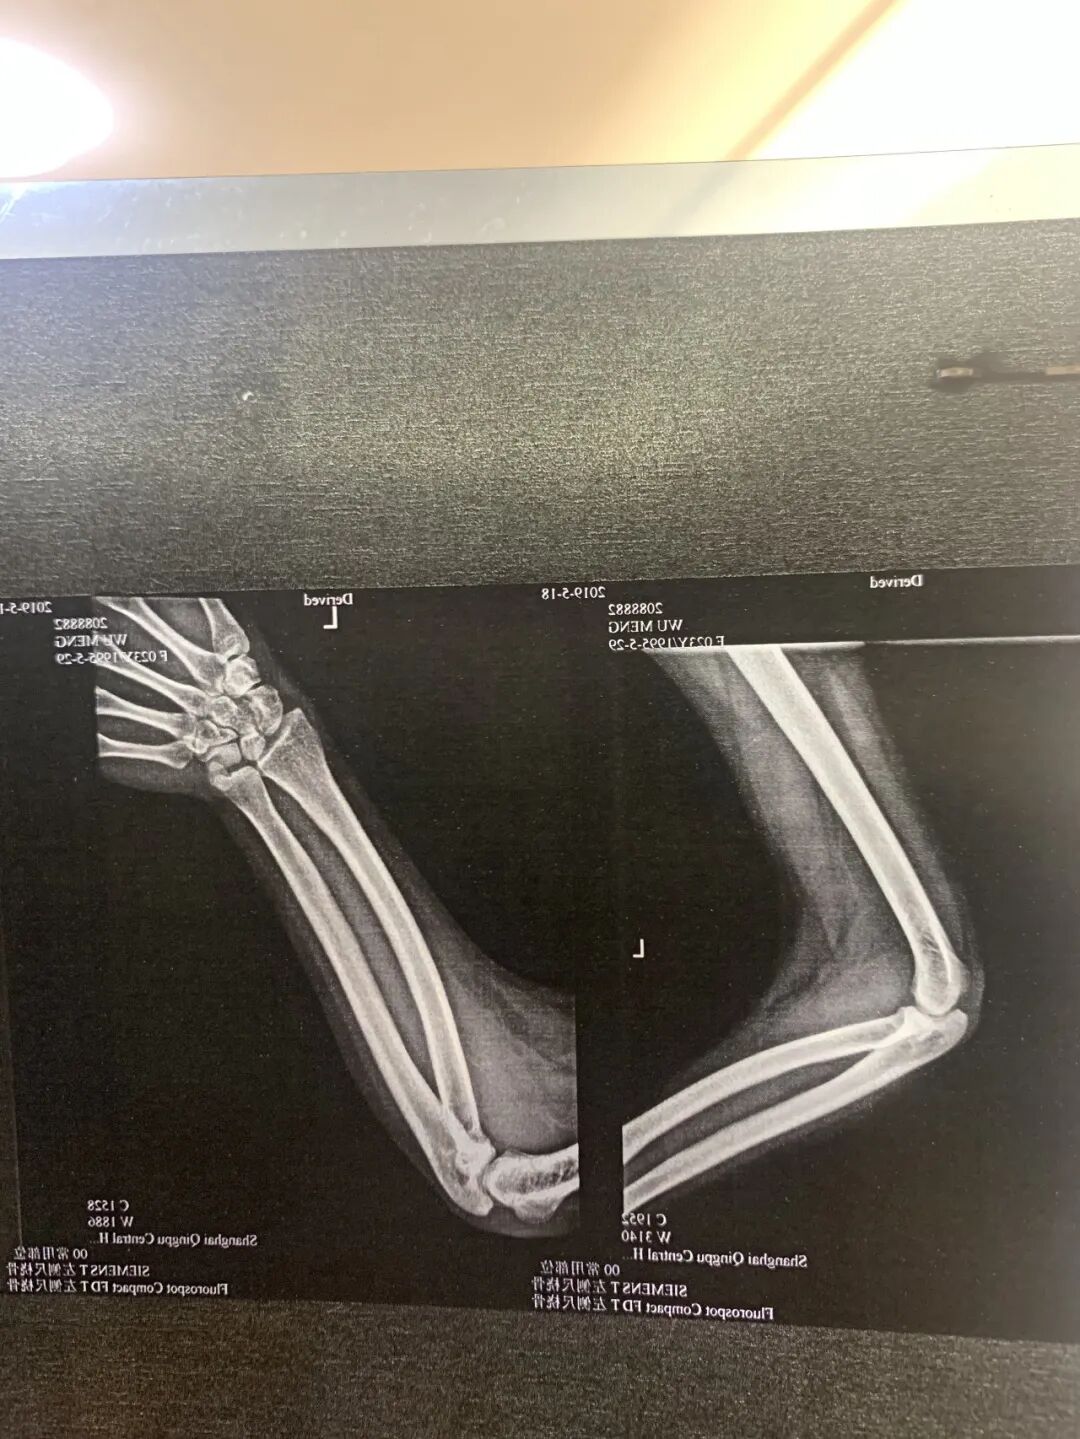

直到2021年底,在尺桡骨病友群群友的建议下,我把自己的情况和湖南省儿童医院杨姓医生说了之后,他告诉我,我的这系列的情况,不像是尺桡骨融合症,而是应该高度怀疑是指甲髌骨综合征。那一刻,萦绕在心中十余年的疑惑,似乎有了一个出口。杨医生告诉我,尺桡骨融合通常只手部的异常,而我的X片看着没有完全融合,更多是脱位,我的异常表现在多方面,且这些方面很有可能是一个病的多种表现。